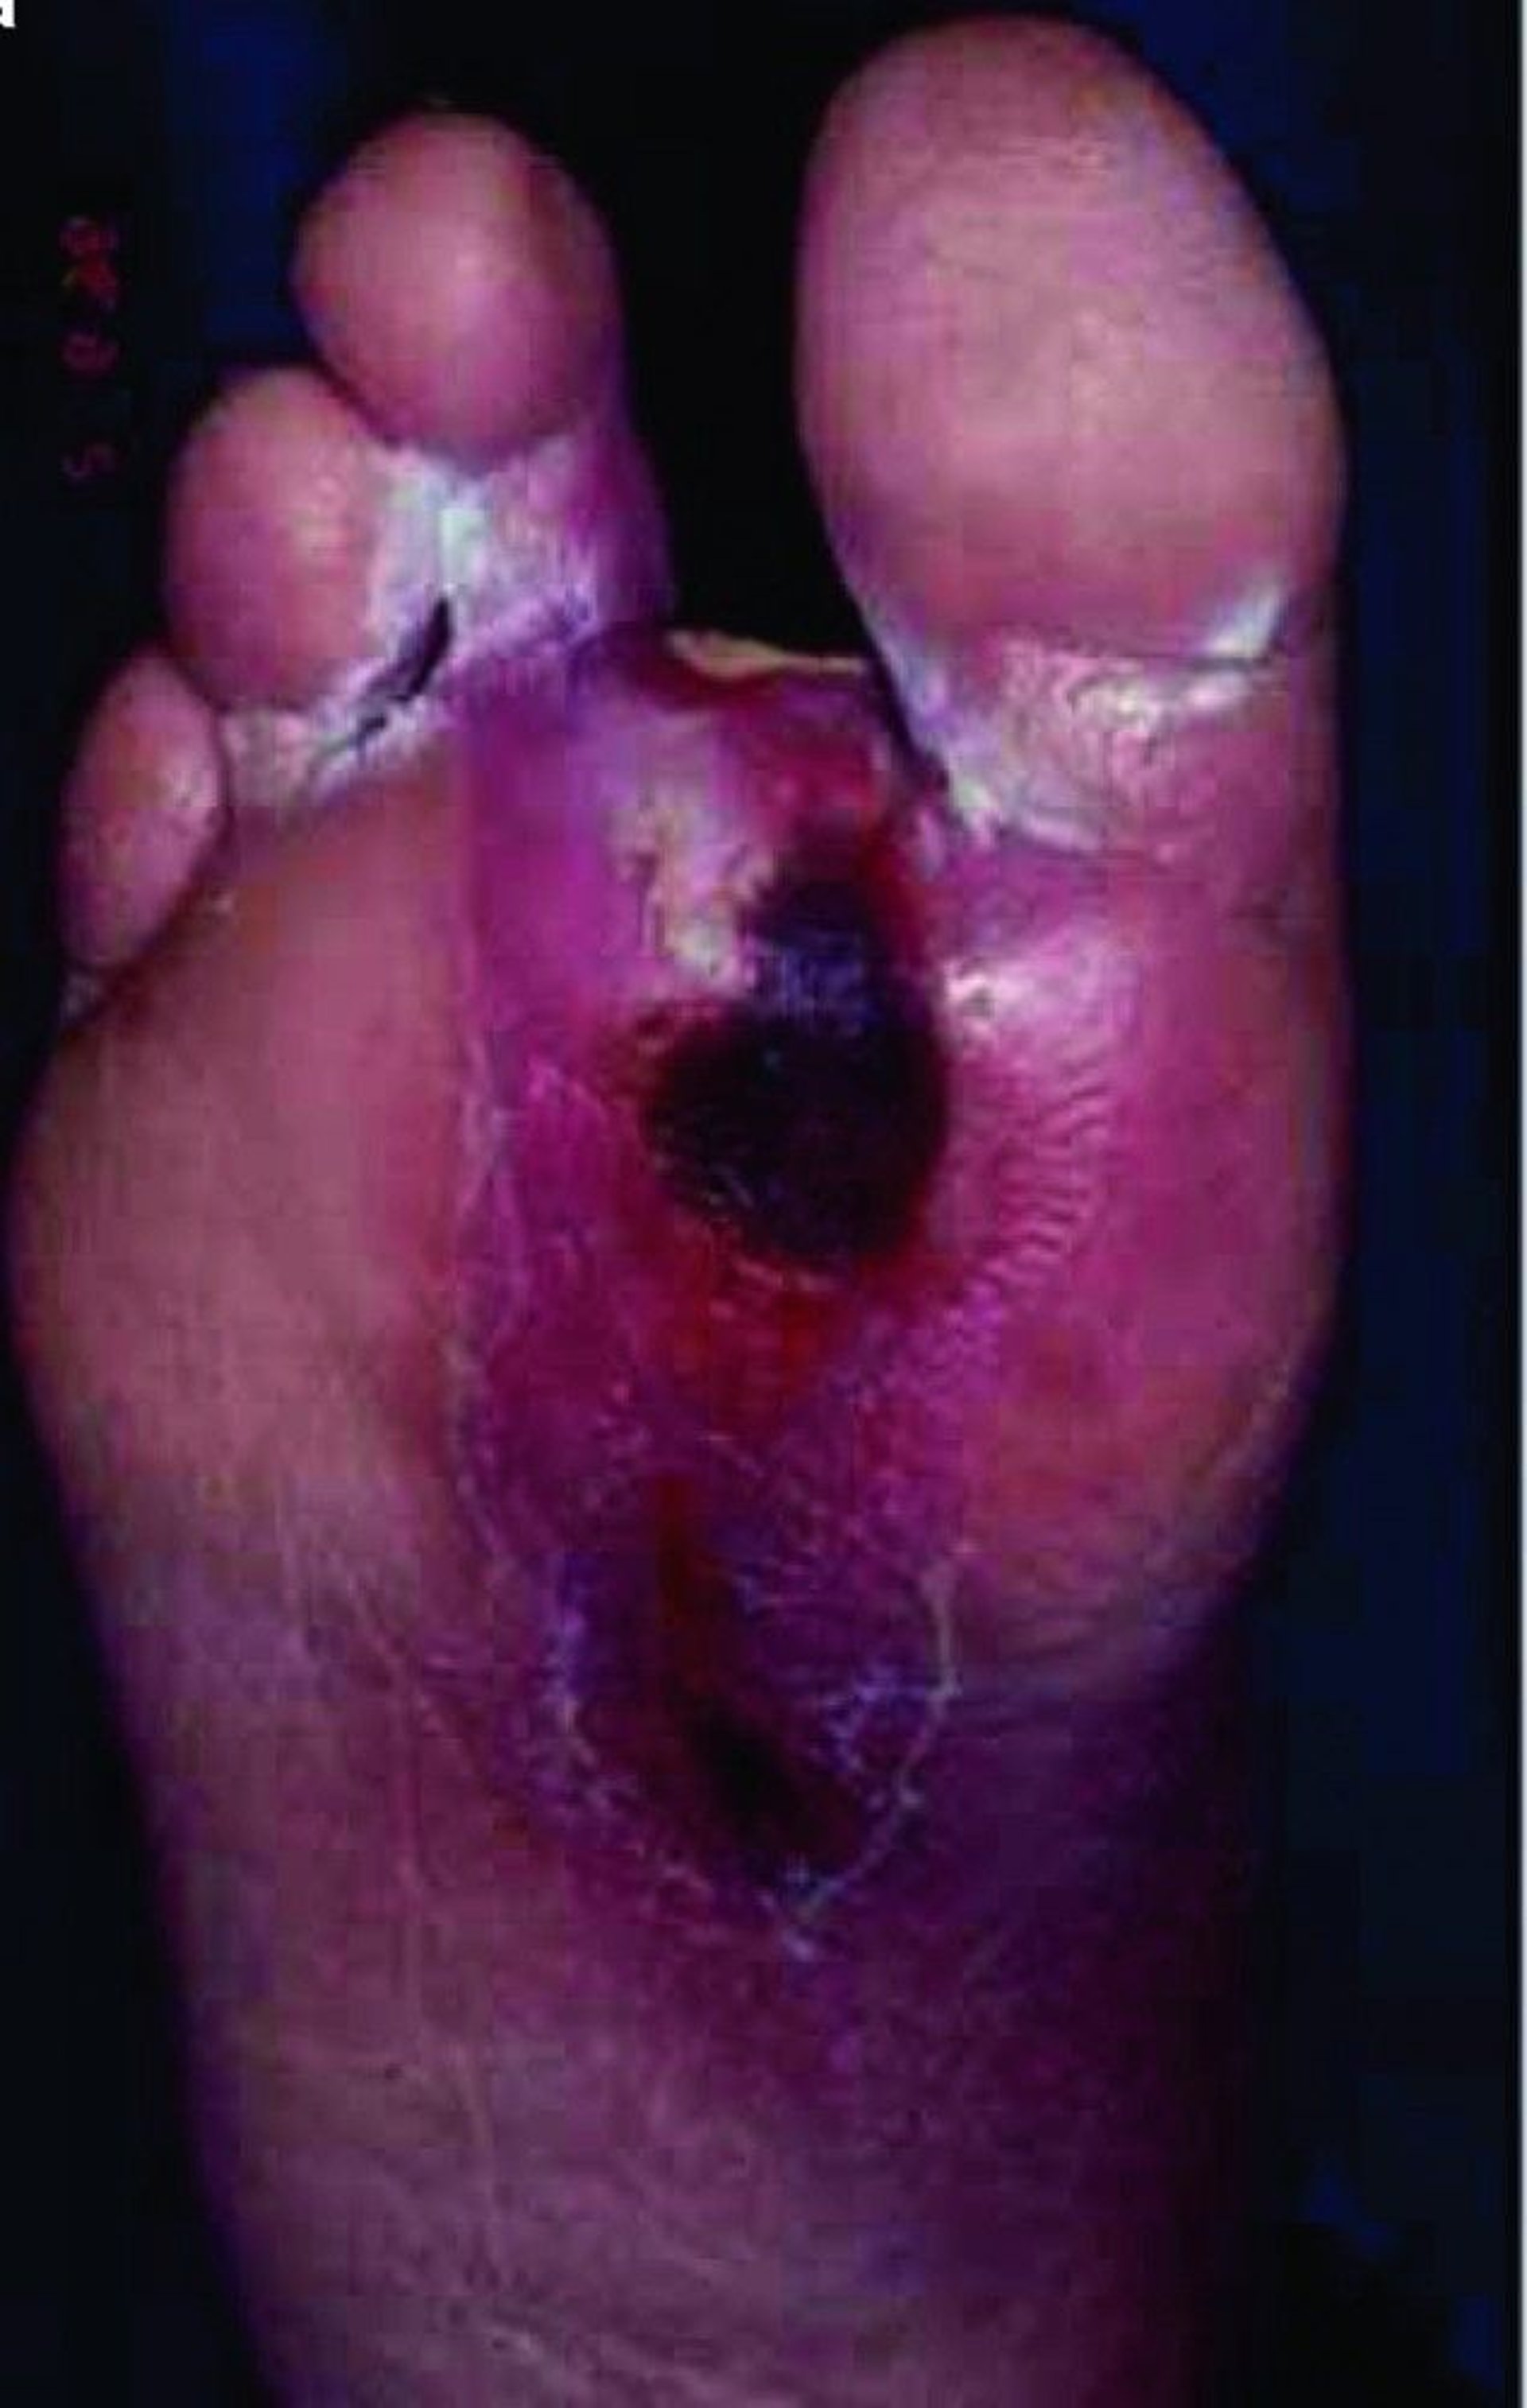

Pengidap diabetes juga sangat mungkin mengalami ulkus (borok) dan infeksi pada kaki dan tungkai karena sirkulasi yang buruk ke kulit. Yang sering terjadi, luka tersebut akan sembuh perlahan atau tidak sembuh sama sekali. Bila luka tidak sembuh, biasanya mereka akan terinfeksi dan hal ini dapat menyebabkan gangrene (kematian jaringan) dan infeksi tulang (osteomielitis). Mungkin memerlukan amputasi pada kaki atau bagian kaki lainnya.

Masalah kaki pada diabetes

Diabetes menyebabkan banyak perubahan pada tubuh. Perubahan kaki berikut ini umum terjadi dan sulit ditangani:

• Kerusakan pada saraf (neuropati) memengaruhi sensasi pada kaki, sehingga tidak merasakan nyeri (mati rasa). Iritasi dan bentuk cedera lainnya mungkin tidak disadari. Cedera dapat terjadi pada kulit sebelum rasa nyeri muncul.

• Perubahan sensasi mengubah cara pengidap diabetes menahan berat badan di kaki mereka, dengan cara memusatkan berat badan di area tertentu sehingga membentuk kapalan. Kapalan (dan kulit kering) meningkatkan risiko kerusakan kulit.

• Diabetes dapat menyebabkan sirkulasi di kaki memburuk, sehingga dapat lebih mungkin mengalami borok ketika kulit mengalami kerusakan dan membuat borok lebih lambat untuk sembuh.

Karena diabetes dapat memengaruhi kemampuan tubuh untuk memerangi infeksi, setelah borok pada kaki terbentuk, hal itu dapat mempermudah terjadinya infeksi. Karena neuropati, seseorang mungkin tidak merasakan ketidaknyamanan akibat infeksi sampai infeksi tersebut menjadi serius dan sulit untuk diobati, yang menyebabkan gangrene. Pengidap diabetes memiliki kecenderungan 30 kali lebih tinggi untuk membutuhkan amputasi kaki daripada orang-orang yang tidak memiliki diabetes.